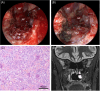

Giant Cell Tumor of the Inferior Turbinate in a 12-Year-Old Child: First Case Report

Keywords: endoscopic sinus surgery; giant cell tumor; nasal cavity.

Figures